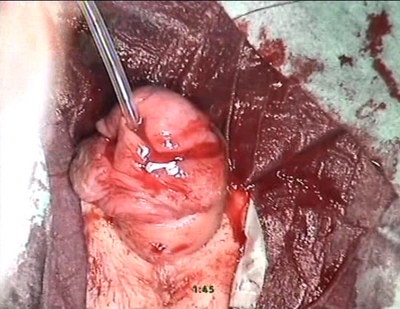

PDS 7/0. Края головки сведены по валярной поверхности над

неоуретрой по методике flip-flap. Края крайней плоти сопоставлены

и сшиты непрерывными швами PDAS 7/0, с элементами деэпидермизации.